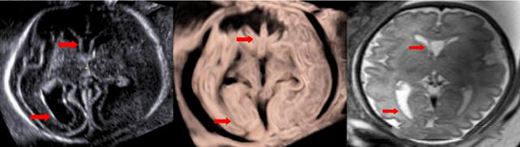

利器2:CrystalVue技術可清晰顯示內部組織結構,如透明隔腔側腦室后角,以及胼胝體,海馬溝等,精準區分組織邊界;

水晶成像顯示透明隔腔側腦室后角

水晶成像顯示胼胝體,海馬溝

此外,在早孕期胎兒中樞神經系統檢查,CrystalVue還能為腦室系統提供全新的三維成像,更早的了解神經發育變化,評估和診斷胎兒中樞神經系統異常;反轉水晶成像更好顯示胎兒大腦溝回。

早孕期 胎兒腦室三維成像